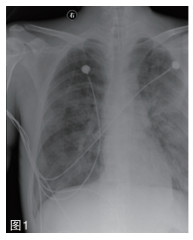

图 3 2016年11月14日胸部CT示:1.双肺弥漫性多发渗出灶;2.左侧胸腔少量气胸,肺组织压缩约5%,继发下叶膨胀不全;3.右侧胸腔少-中量积液,双肺多发肺大泡。 |

补液消酮、胰岛素控制血糖等对症支持治疗。11月3日患者酮症逐渐好转,但酸中毒进行性加重,最重时血气分析:PH 6.822,PCO2 21.4 mmHg,BE -27.7 mmol/L。最高体温39℃,并伴有患者神志改变,烦躁。左侧腹股沟伤口分泌物首次培养回报革兰阴性(G-)杆菌。予行左侧腹股沟伤口脓肿切开引流、气管插管、有创呼吸机辅助通气及床旁血液净化等ICU多脏器功能支持治疗。11月6日,患者血培养及伤口分泌物再次培养回报:类鼻疽伯克霍尔德氏菌(Burkolderia pseud-omallei, BP)。为求进一步明确,请实验室对患者腹股沟分泌物、血培养分离得到的2株细菌进一步鉴定,确认为同一菌种即类鼻疽伯克霍尔德菌。药敏试验仅对头孢他啶及亚胺培南敏感。两次查血G试验均明显升高,结合患者既往有糖尿病病史,不排外存在侵袭性全身真菌感染可能,治疗方案上调整抗生素为亚胺培南+氟康唑。2周后,患者体温逐渐降至正常,左侧腹股沟伤口愈合良好,血气、感染指标及肺部感染情况较前明显好转(如图 3)。给予降阶梯治疗,调整抗生素为头孢他啶1.5g q6h。21日患者突发胸闷、气促,伴大汗。急诊床旁彩超可见左侧胸膜滑动征消失及沙滩征(如图 4),胸片提示左侧大量气胸(压缩约90%)(如图 2)。11月27日再次出现胸闷气促,胸片提示右侧大量气胸(压缩约90%),治疗上予胸腔闭式引流术、肺复张、机械通气、足疗程抗感染、器官功能维持等。复查胸部CT变化(如图 5)。12月12日患者症状好转,成功撤机,拔除气管导管、转出急诊ICU至急诊观察病区。转出诊断:1.左侧腹股沟皮下脓肿;2.脓毒性休克;3.重症肺炎;4.糖尿病酮症酸中毒;5.多器官功能障碍综合征MODS(ARDS、AKI、DIC);6.双侧液气胸。患者与12月24日好转出院。